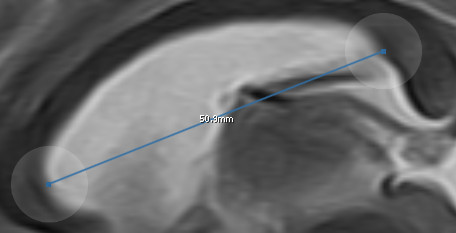

11.1.4. Messungen

Mit dem Measurement-Werkzeug ![]() können Sie Messungen in einem Schichtbild durchführen.

Für die Darstellung der Messgenauigkeit wird eine Nachkommastelle verwendet.

Die eingefügte Messung kann über "Pinch-to-Zoom" vergrößert oder verkleinert werden.

Alternativ können auch nur einzelne Enden unabhängig voneinander manipuliert werden.

Dazu müssen Sie die transparenten Kreise am Ende der Messung bewegen.

Sie können mehrere Messungen in einem Bild durchführen und mit einem Tap oder im Annotations-Menü erneut auswählen.

Die markierte Messung wird orange eingefärbt.

können Sie Messungen in einem Schichtbild durchführen.

Für die Darstellung der Messgenauigkeit wird eine Nachkommastelle verwendet.

Die eingefügte Messung kann über "Pinch-to-Zoom" vergrößert oder verkleinert werden.

Alternativ können auch nur einzelne Enden unabhängig voneinander manipuliert werden.

Dazu müssen Sie die transparenten Kreise am Ende der Messung bewegen.

Sie können mehrere Messungen in einem Bild durchführen und mit einem Tap oder im Annotations-Menü erneut auswählen.

Die markierte Messung wird orange eingefärbt.